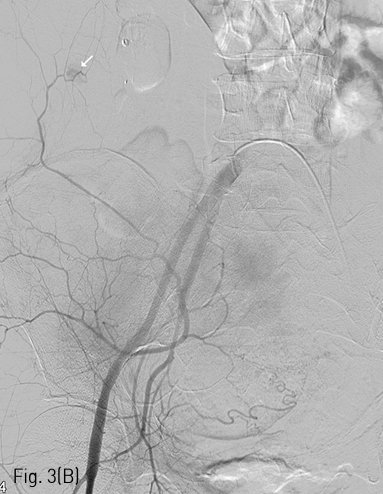

Fig 3A

(A) 4 days later, more size increase and another active bleeding focus of the right abdominal wall hematoma were noted on follow-up abdomen CT. New hematoma at left side of the abdominal wall without any definite detected bleeding focus on the CT scan.

Fig 3B

(B) Extravasation of contrast media from the iliolumbar artery of the posterior division of the right internal iliac artery was successfully treated with glue embolization.